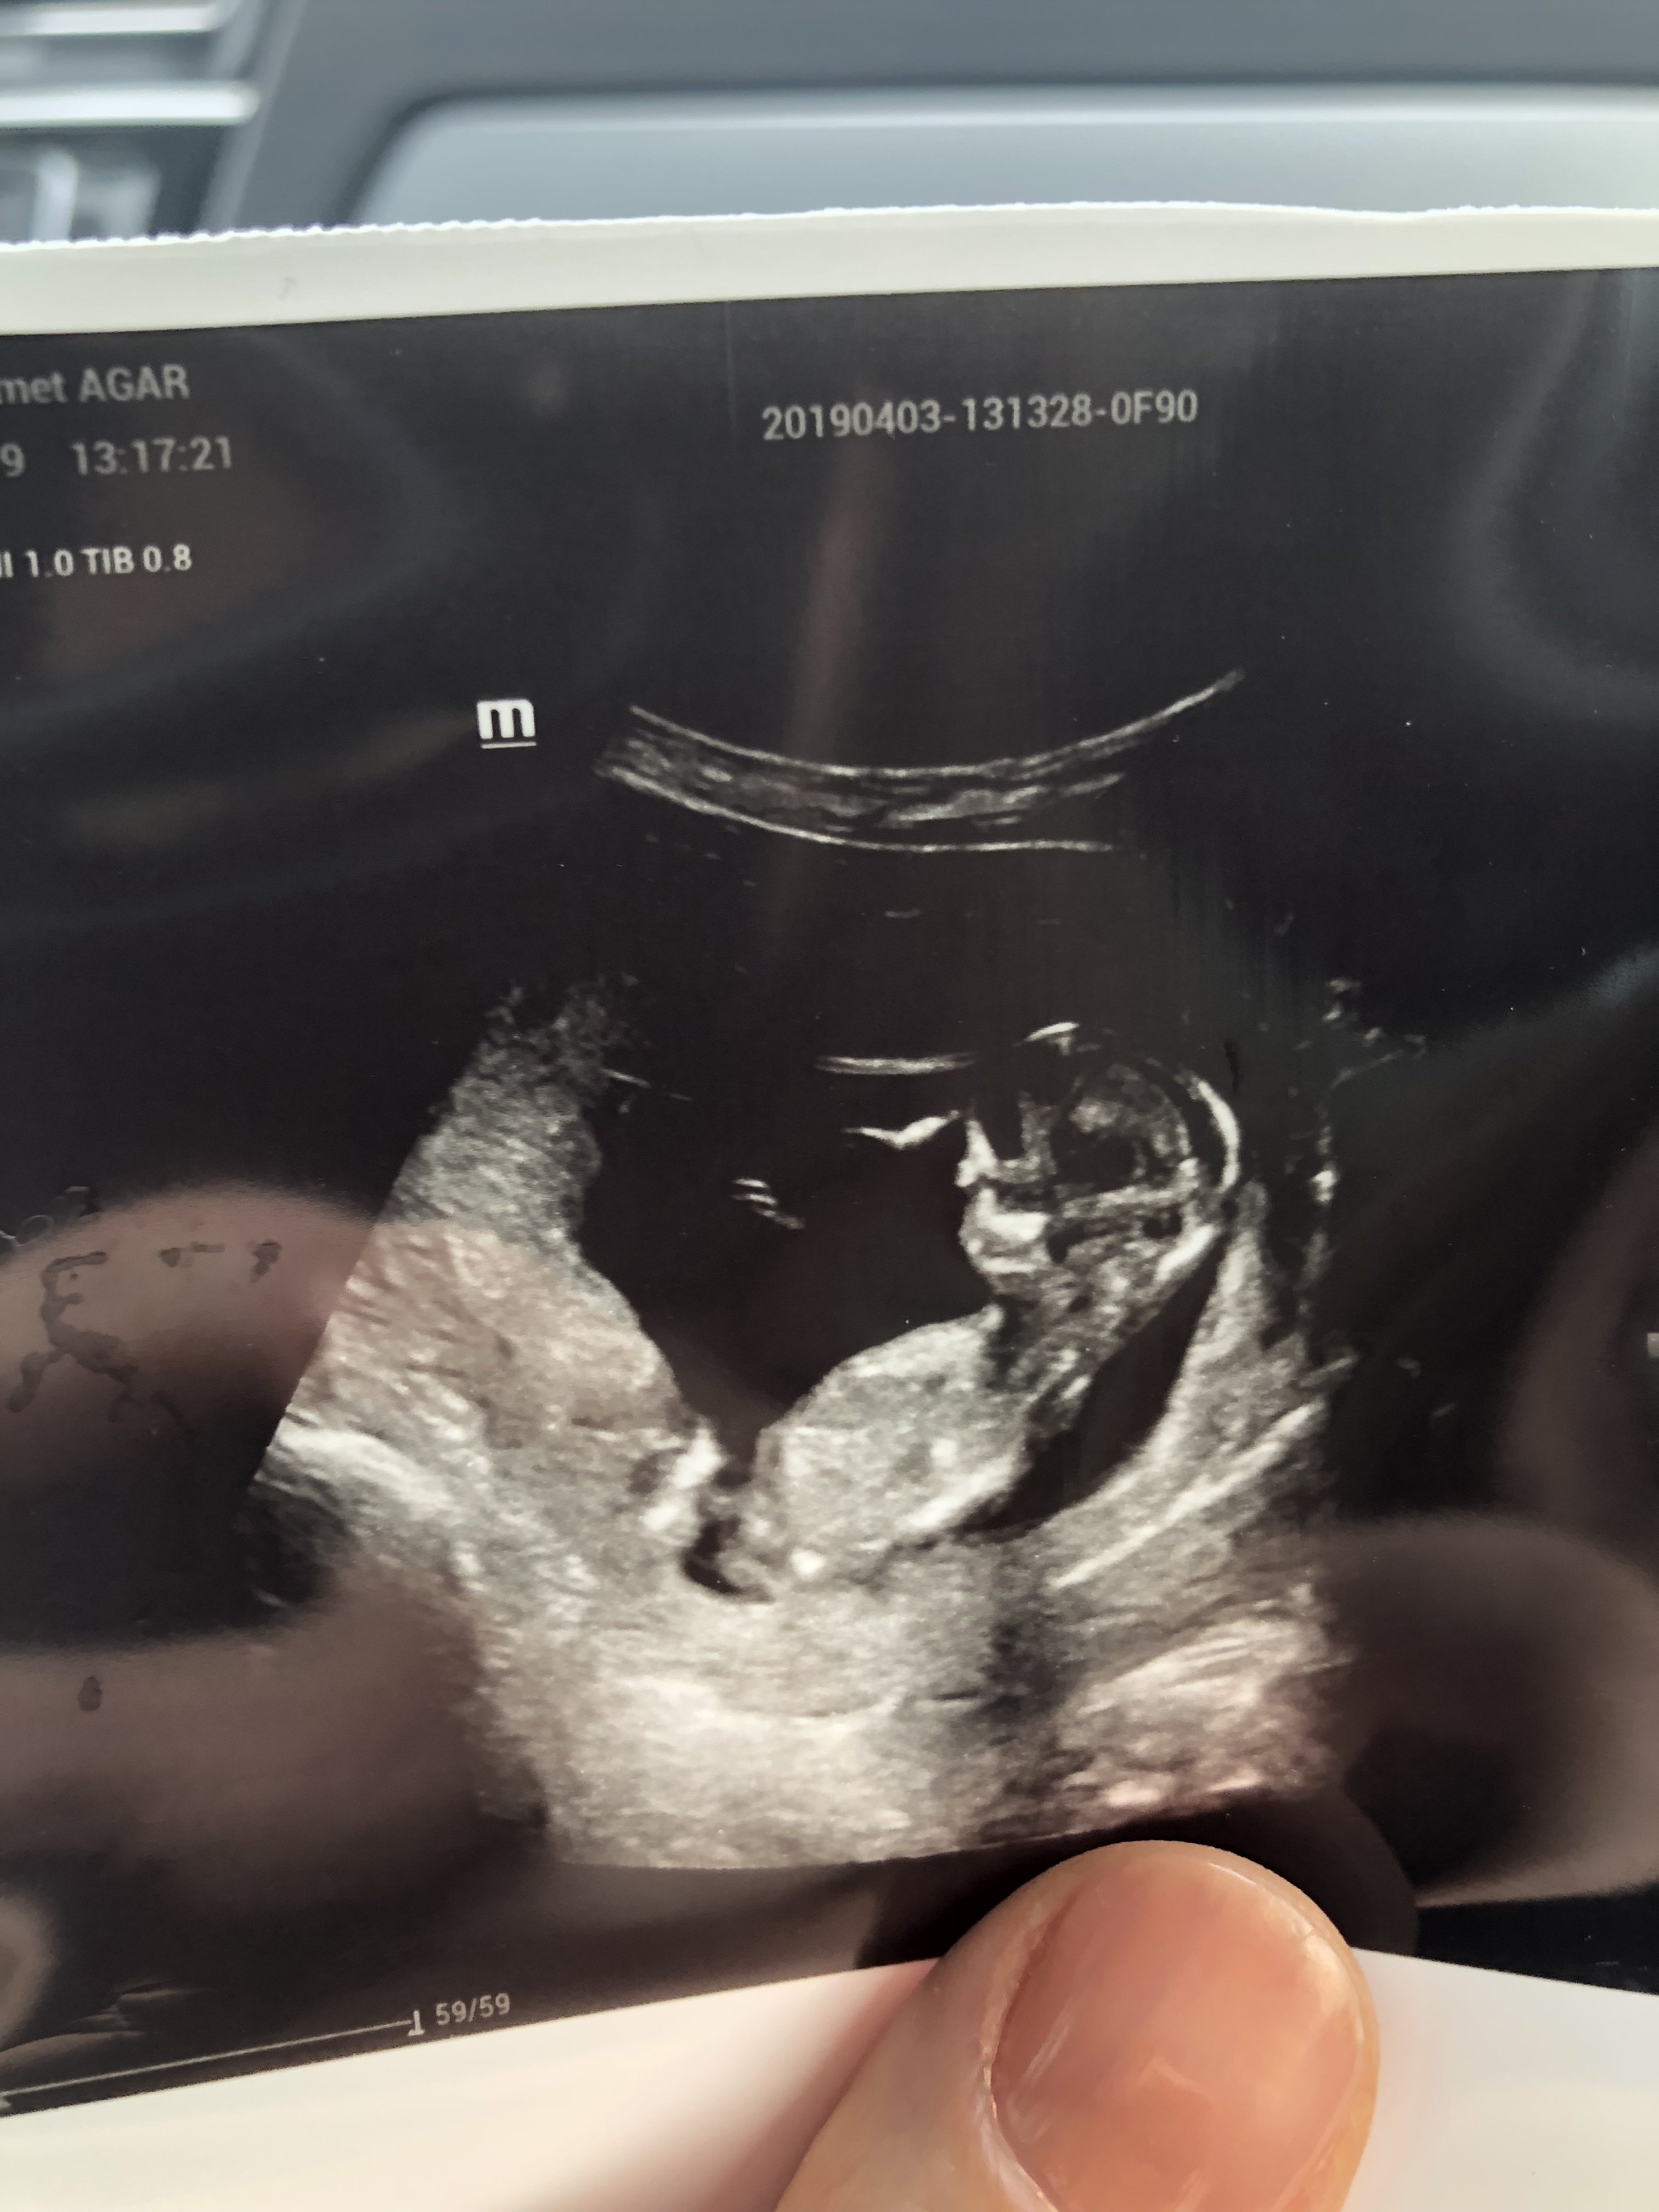

G gmz_cm Yeni Üye Üye 15 Nisan 2019 #595 gmz_cm' Alıntı: Ekli dosyayı görüntüle 85264Ekli dosyayı görüntüle 85264 Benim bebişimin cinsiyetine de bakabilir misiniz Genişletmek için tıkla ...

gmz_cm' Alıntı: Ekli dosyayı görüntüle 85264Ekli dosyayı görüntüle 85264 Benim bebişimin cinsiyetine de bakabilir misiniz Genişletmek için tıkla ...

B Boncuk23 Yeni Üye Üye 16 Nisan 2019 #596 Sevimli cadı' Alıntı: Nub çıkıntısı belli olmuyor doktor konumuna göre değerlendirme yapmıştır . Doktor cinsiyetini görebildi mi? Genişletmek için tıkla ... Merhaba rica etsem benim ultrason fotolarıma da bakabilir misiniz teşekkürler Ekli dosyalar 20190411_231719.jpg 859,8 KB · Görüntüleme: 977 20190411_231635.jpg 1.003,5 KB · Görüntüleme: 693 20190411_231645.jpg 1 MB · Görüntüleme: 755 20190411_231635.jpg 1.003,5 KB · Görüntüleme: 768

Sevimli cadı' Alıntı: Nub çıkıntısı belli olmuyor doktor konumuna göre değerlendirme yapmıştır . Doktor cinsiyetini görebildi mi? Genişletmek için tıkla ... Merhaba rica etsem benim ultrason fotolarıma da bakabilir misiniz teşekkürler